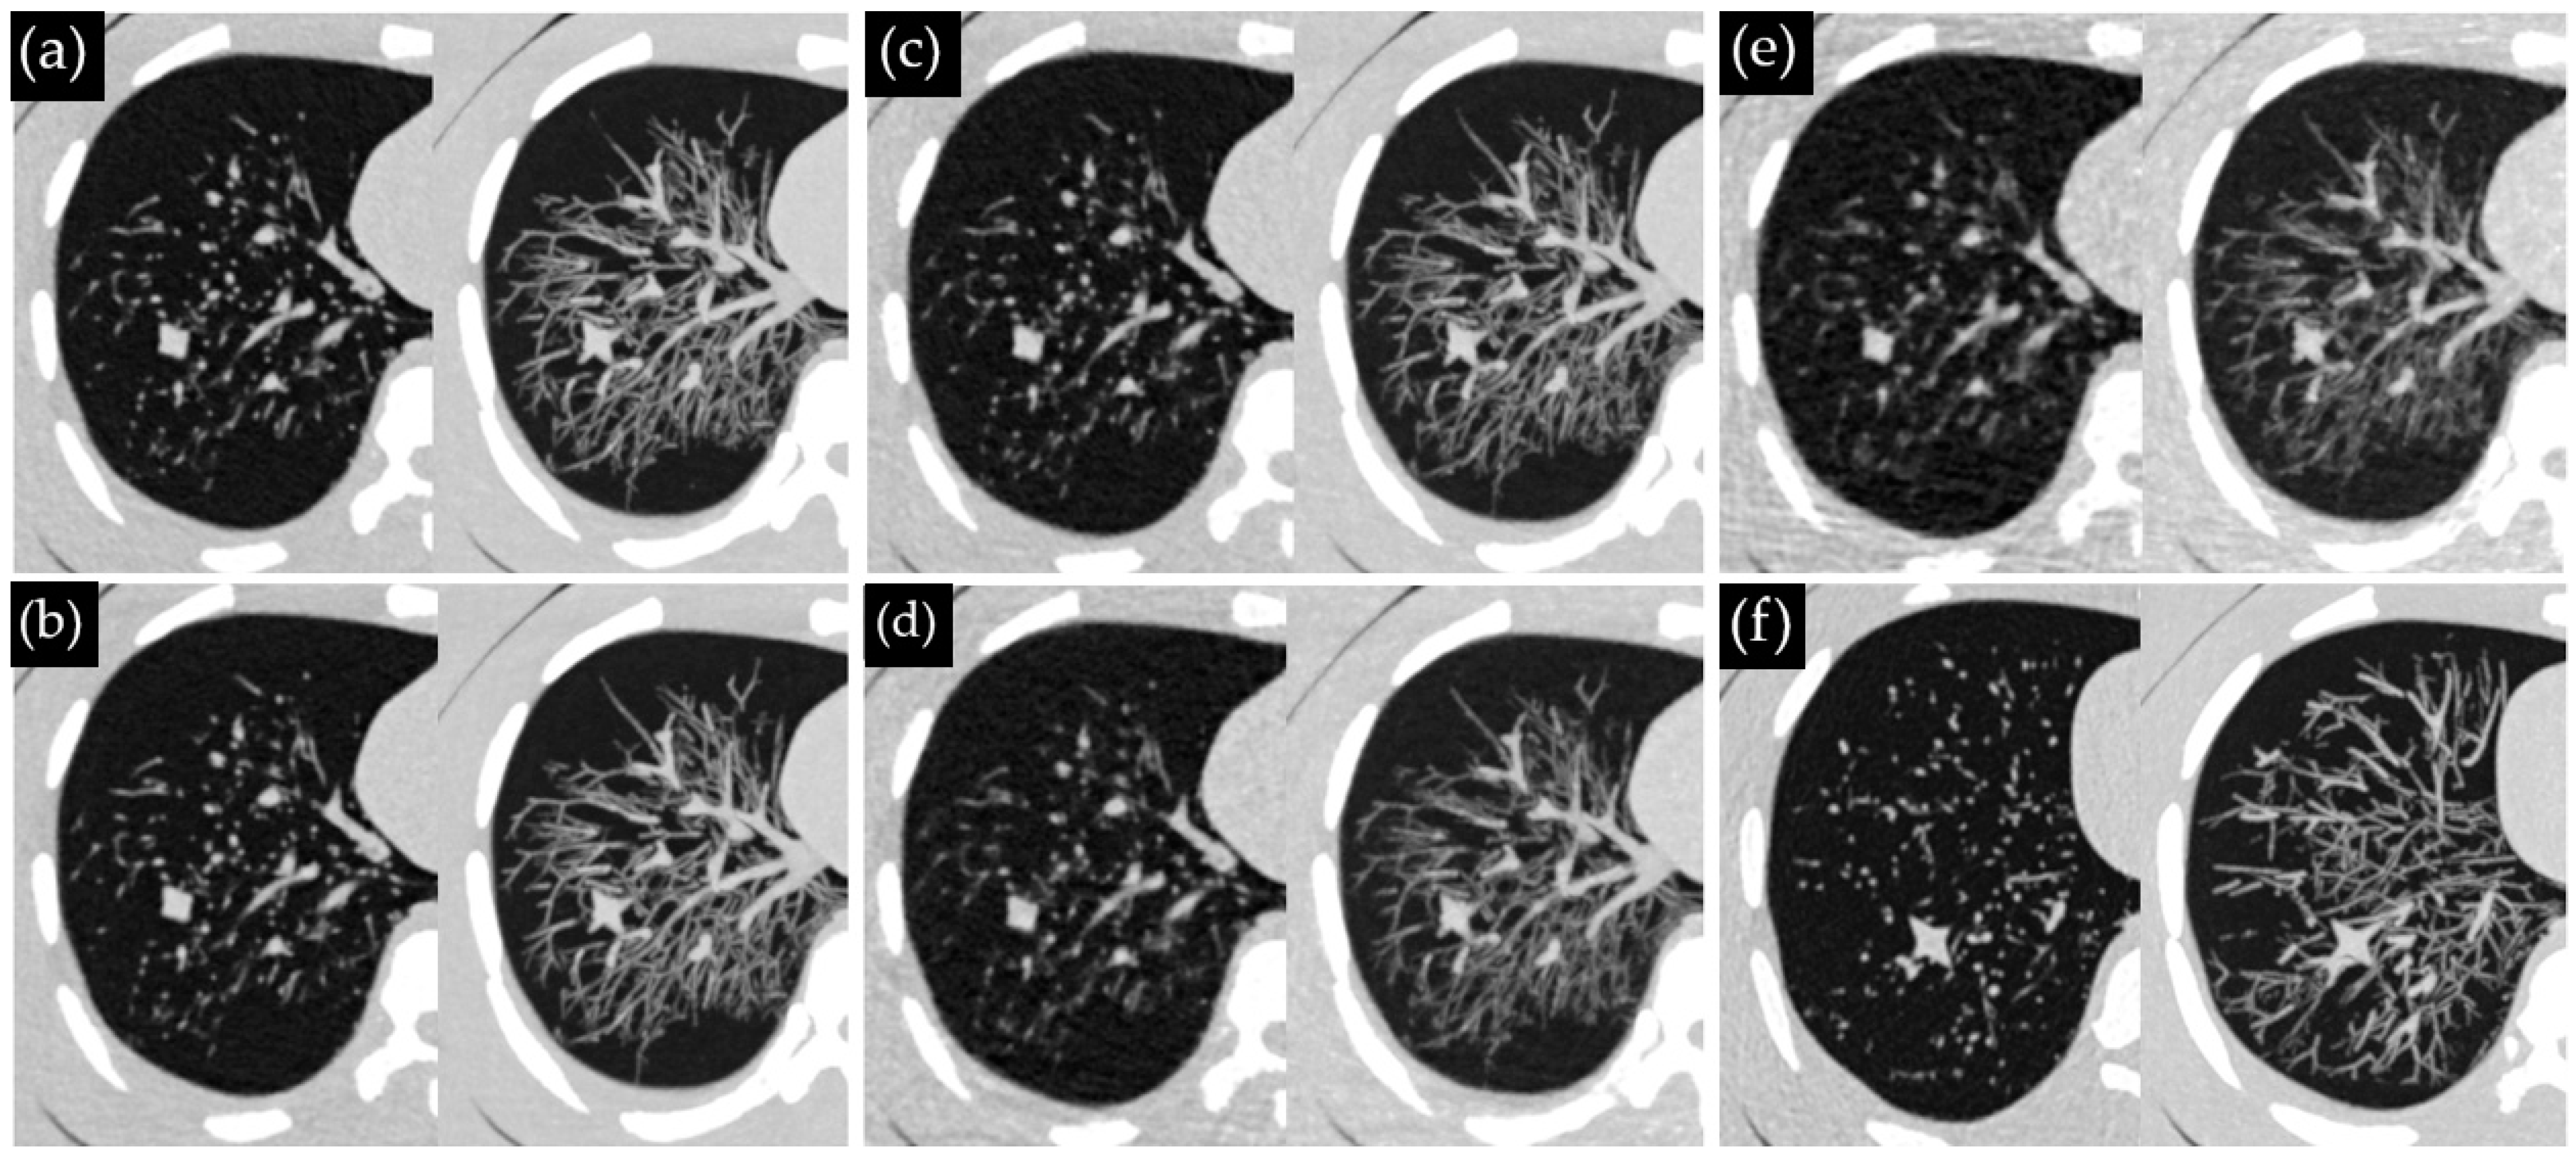

2.1. Phantom and Nodules

2.2. CT Systems and Protocols

2.3. CT Acquisitions